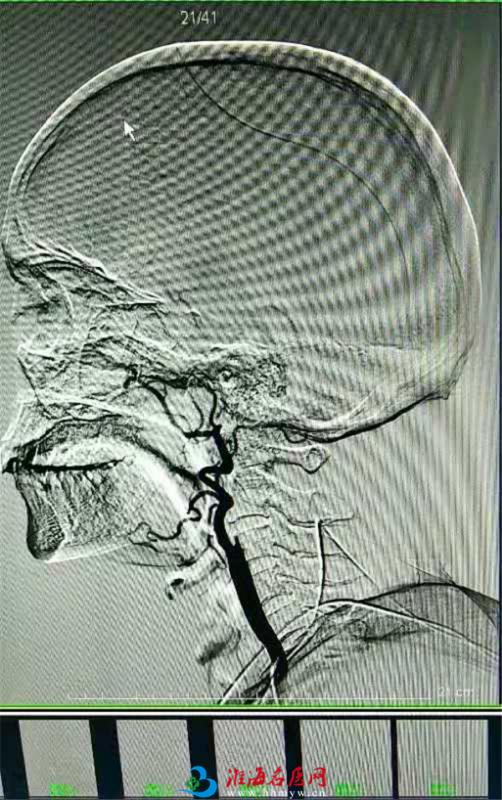

10月21日中午,急诊室的电话打来:“急诊室有病人,男性,66岁,突发言语不清伴右侧肢体无力9小时,目前意识不清,病情还在加重,请您立即前往会诊!”接到急诊通知的卒中团队值班人员立刻进入备战状态,朱士光副主任医师为病人查体:患者言语不能,意识障碍进行性加重,右上肢肌力1级,右下肢肌力4级。经过与家属的沟通后,朱士光副主任医师率领卒中团队为患者立即实施脑血管造影术+动脉取栓术。经过1个小时的紧张手术,血栓被取出,患者被送回病房。四十病区医护人员严阵以待,密切观察病情。次日清晨,患者意识较前有明显好转,吐字也清晰了,右上肢的肌力达到了3级,右下肢肌力恢复到5级。 10月26日,患者肌力恢复正常,看着他能够走来走去,我们都感到十分欣慰。几天后,经过后续的治疗,老人康复出院了。看着能够正常交流、行走的老人,家属双手合十,脸上写满了感激。